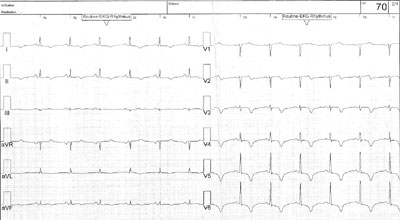

Eine 61-jährige, gesunde Patientin erleidet einen Skiunfall mit kurzer Bewusstlosigkeit. Ein Schädel CT ergibt keine Hinweise für intrakranielle Pathologien.

Vorgängig wurden weder eine Angina pectoris noch Palpitationen beklagt. Bei Spitaleintritt zeigt sich nebst erhöhten kardialen Biomarkern folgendes EKG:

Wie interpretieren Sie das EKG?